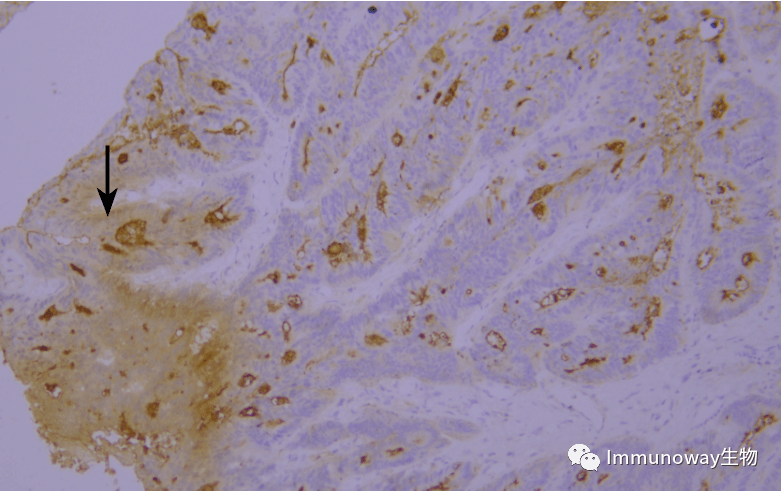

采用ihc检测her-2结果的判读